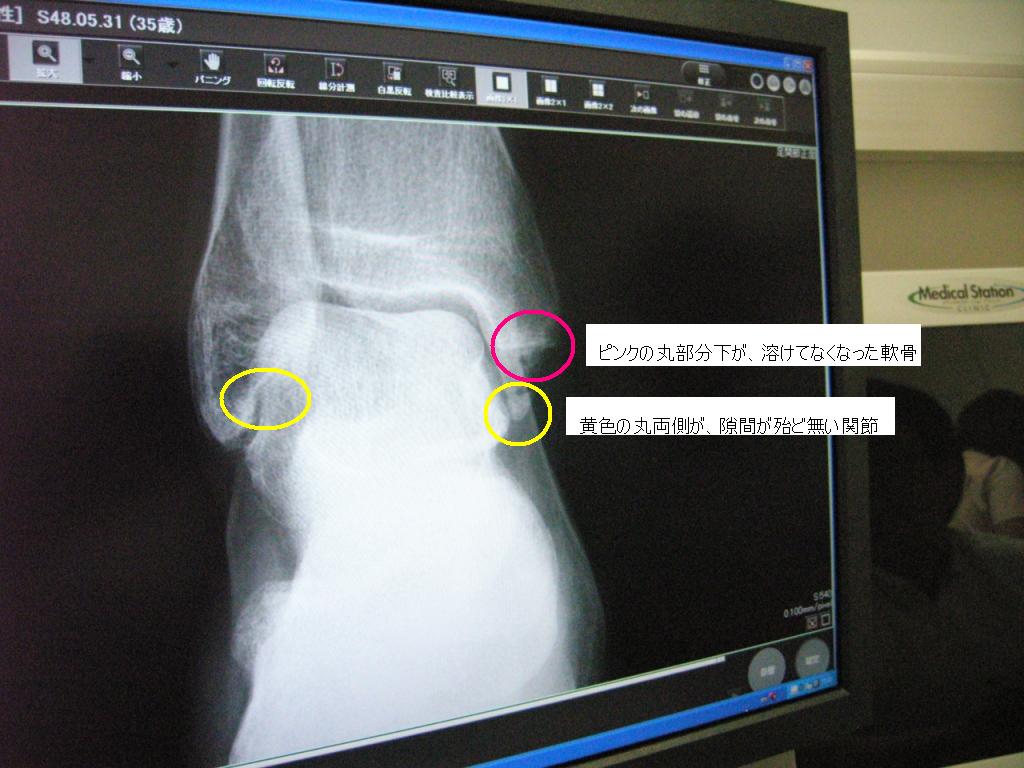

◆無くなった郷の軟骨っ♪

先生様『ほらここ、右足首クルブシの下スッポリ溶けてるね』

ガビーン _│ ̄│○ 郷の骨がお肉に変化じゃ

ショックに追い討ちをかけるように、足首の左右にある間接の隙間が殆んど無い状態であることを告げられる。

写真のとおりじゃ♪

ピンクの丸で囲んだところを見てクリリン

真一文字(横線)の下にほんらいは三角形の軟骨があるのじゃが、段のようになり、すっぽり無くなってしまってるのよ♪

郷吉ショックじゃった。あぃ